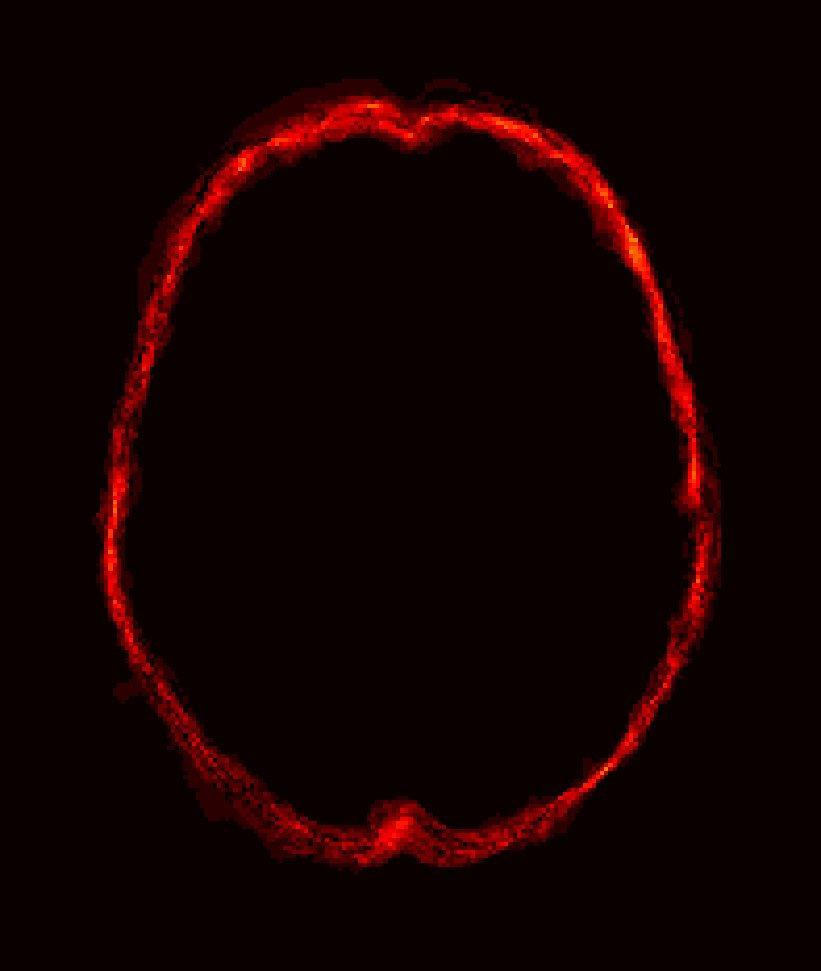

Fig. 9 (left) visualizes the average brain mask errors for IBSR and LPBA40. All images are first affinely registered to the atlas. Then we transform the gold-standard expert segmentations as well as the automatically obtained brain masks of the different methods to atlas space. We compare the segmentations by counting the average over- and under-segmentation errors over all cases at each voxel. This results in a visualization for areas of likely mis-segmentation. Our PCA model, ROBEX, BEaST (BEaST*) and BET perform well on these two datasets. Compareed to our model, ROBEX, BEaST (BEaST*) and BET show larger localized errors, e.g., at the boundary of the parietal lobe, the occipital lobe and the cerebellum. While MASS, BSE and CNN perform well on the LPBA40 dataset, they perform poorly on the IBSR dataset. This is in particular the case for the CNN approach.

Finally, Fig. 9 (right) shows the average segmentation errors on the BRATS and TBI datasets: our PCA method shows fewer errors than most other methods in these two abnormal datasets. MASS also shows few errors, while ROBEX, BEaST (BEaST*) and BET exhibit slightly larger errors at the boundary of the brain. CNN and BSE particularly show large errors for the BRATS dataset presumably again due to the coarse resolution of the BRATS data.

Figure 9: Examples of 3D volumes of average errors for the normal IBSR and LPBA40 datasets, as well as for the pathological BRATS and TBI datasets. For IBSR/BRATS, we show results for BEaST*. Images and their brain masks are first affinely aligned to the atlas. At each location we then calculate the proportion of segmentation errors among all the segmented cases of a dataset (both over- and under-segmentation errors). Lower values are better (a value of 0 indicates perfect results over all images) and higher values indicate poorer performance (a value of 1 indicates failure on all cases). Clearly, BSE and CNN struggle with the BRATS dataset whereas our PCA method shows good performance across all datasets.